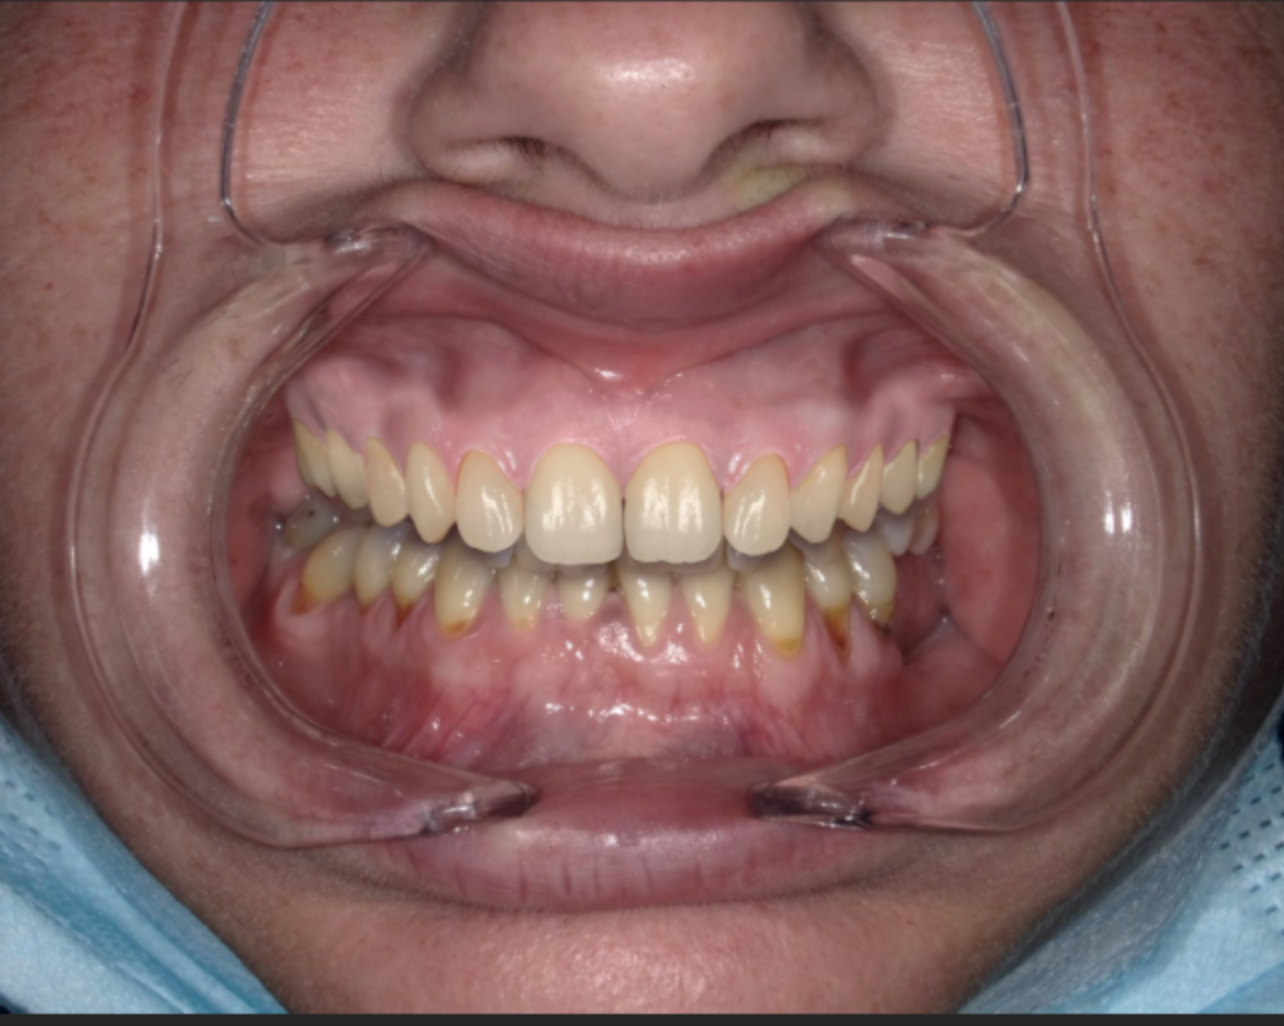

Le chirurgien-dentiste va utiliser la même démarche qu’un architecte, à savoir la réalisation d’un ensemble de mesure : les photos, les empreintes 3D, les radiologies, et grâce au logiciel adapté.

Le Smile Design va permettre de réaliser un diagnostic précis des problématiques esthétiques et fonctionnelles rencontrées par notre patient de manière à trouver le projet de traitement le plus adapté aux demandes de notre patient. Il s’agit donc de réaliser une SIMULATION du résultat attendu.